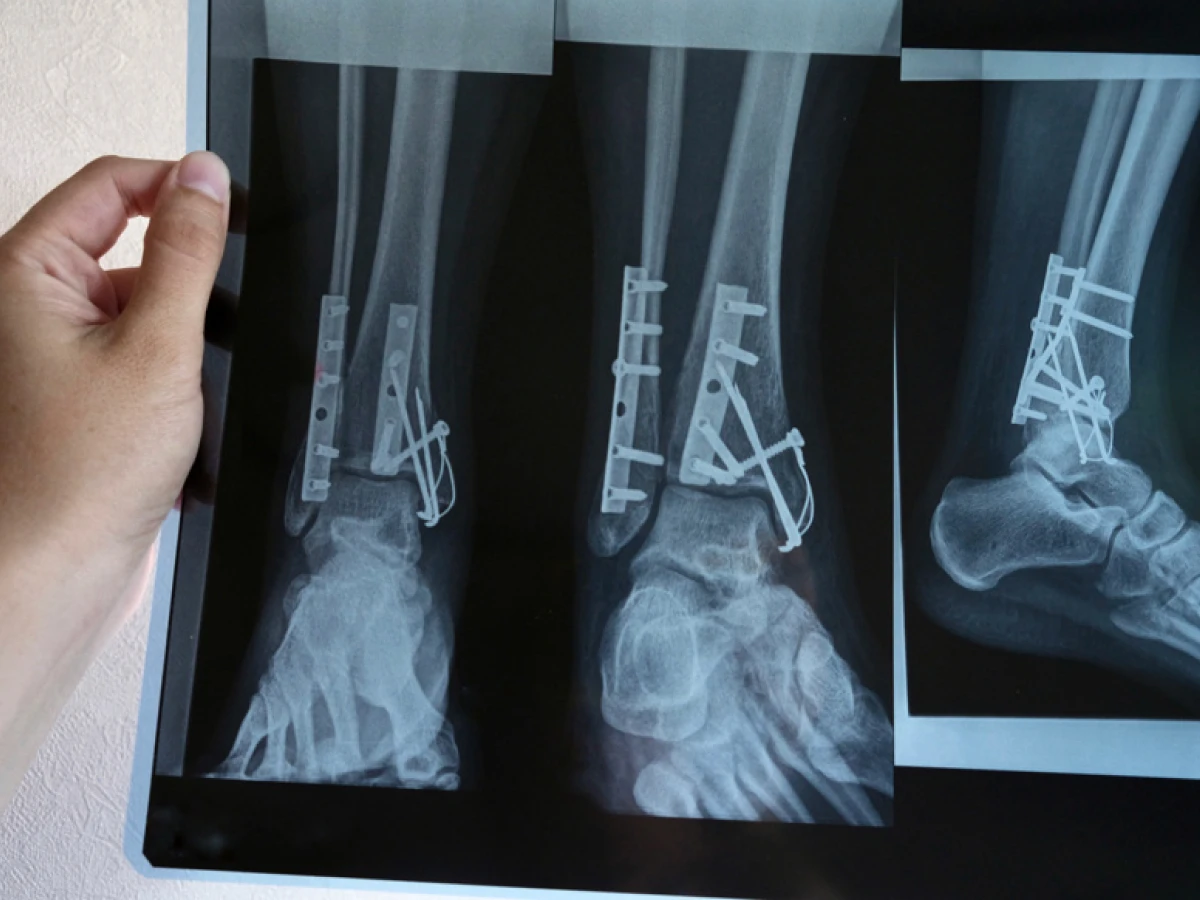

Ведущий метод диагностики поражения — рентгенография. Костная ткань хорошо пропускает рентгеновские лучи. Вплоть до малейших деталей отражается на полученных снимках. Специалист изучает характер поражения. Либо сразу определяет тактику лечения, либо направляет пациента на дальнейшее обследование.

Более точный, чем стандартная рентгенография метод диагностики переломов костей — компьютерная томография. Основан он также на прохождении через ткани рентгеновских лучей. Только отражаются они уже не на 2 снимках, а на томограммах, с величиной среза всего несколько миллиметров. У травматолога появляется возможность рассмотреть и углы стояния отломков, и плотность тканей, и все прочие важные для лечения моменты. Выбрать наилучшую тактику ведения конкретного пациента.

- Открытая операция. Второй вариант оперативного лечения — остеосинтез. Это уже открытая операция. Проводится она под общей анестезией. Травматолог расскажет кожу, мягкие ткани, получает доступ к костным фрагментам, фиксирует их с помощью металлической конструкции в заданном положении. Опять же, между близко расположенными отломками разрастается костная мозоль.